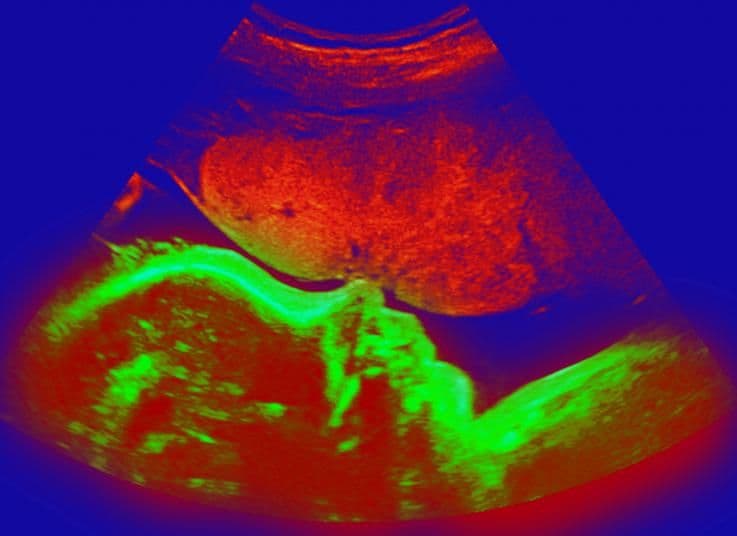

The placenta, shown in red above the baby’s green profile, is now receiving 0.5 litre (18fl oz) of blood each minute from your circulation. In order to accommodate this increase your blood volume expanded dramatically in the first few months of pregnancy.